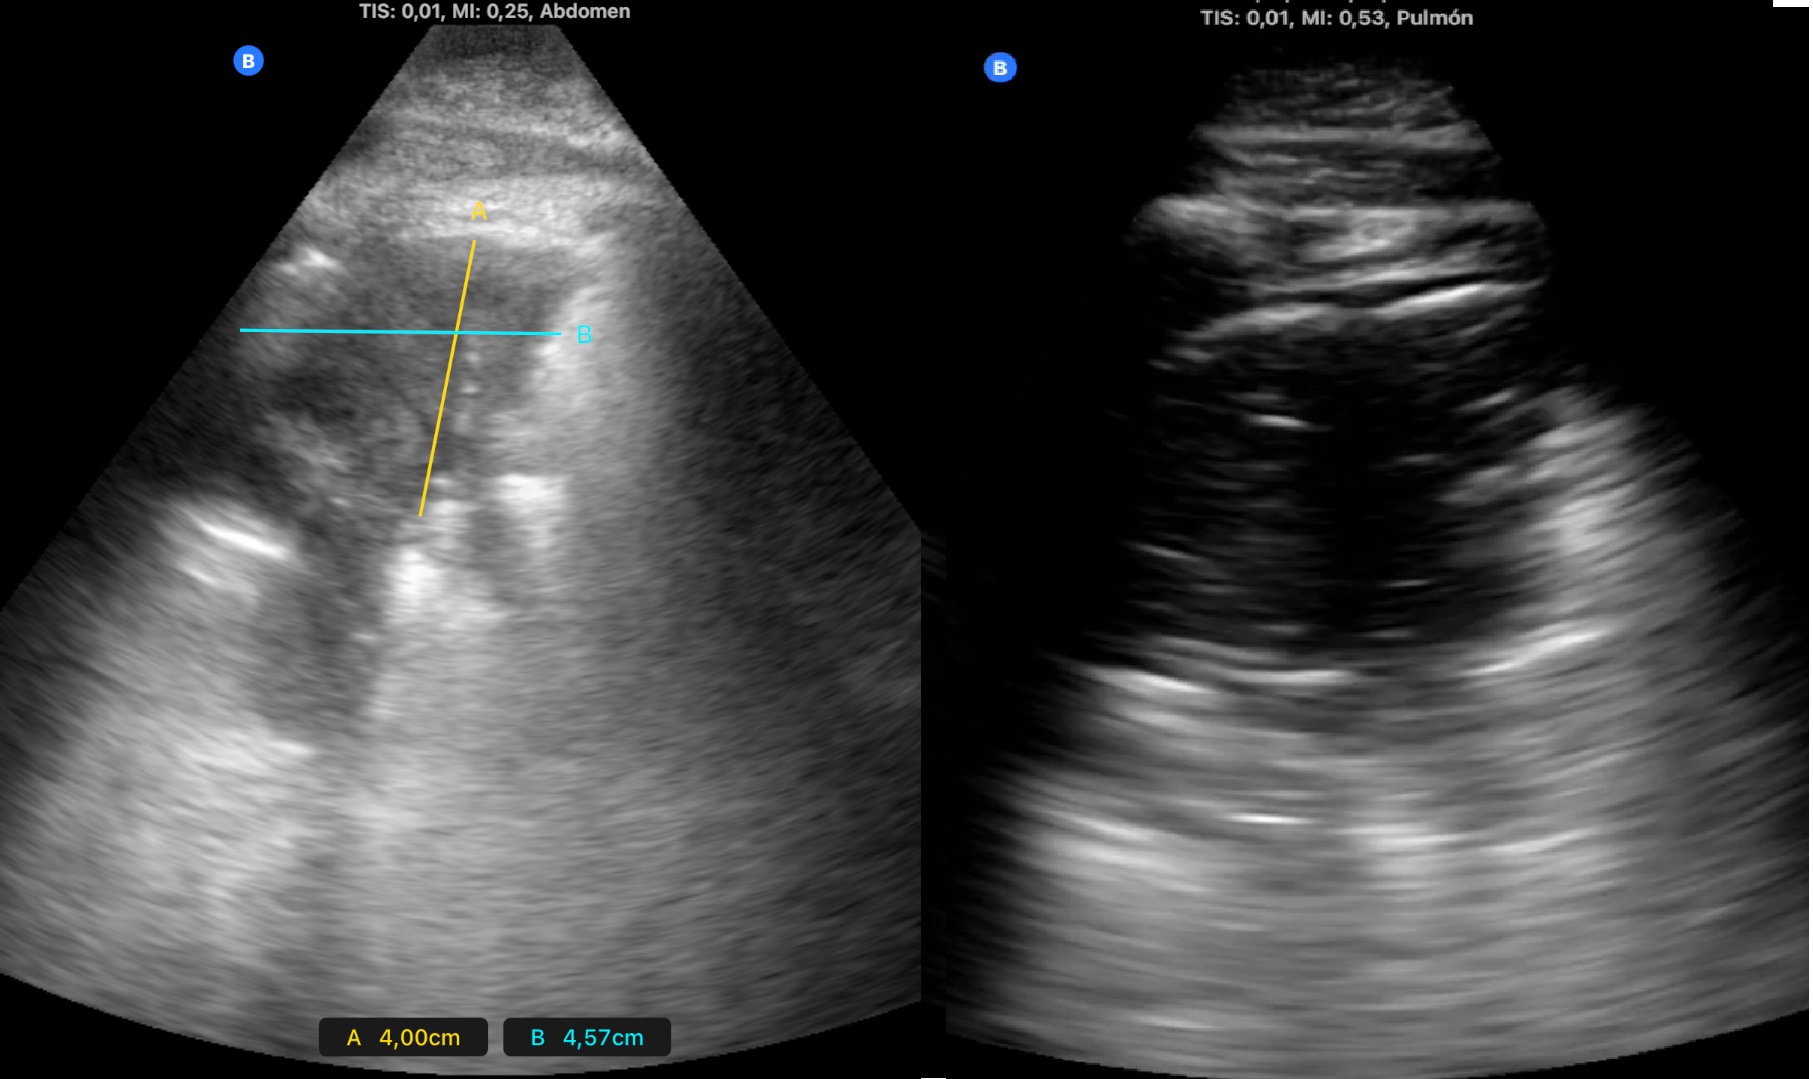

Se hace ecografía pulmonar en ambos casos.

Descripción de los hallazgos ecográficos y las imágenes más relevantes para la resolución del caso

Desaparición de síntomas en los primeros dos días. Seguimiento ecográfico que muestra la desaparición de la neumonía a los 15 días en el primer caso y reducción paulatina del tamaño de la lesión en el segundo.

Se trata de dos casos en los que los hallazgos clínicos y las pruebas complementarias convencionales no hubieran llevado al diagnóstico ni tratamiento adecuados. En el primer caso por una radiografía normal y en el segundo por sintomatología no sospechosa que podría no haber indicado dicha radiografía. La disponibilidad de ecógrafo en la consulta facilita su utilización de inmediato tras la auscultación, detectando las lesiones y consiguiendo una mayor precisión diagnóstica y terapéutica.